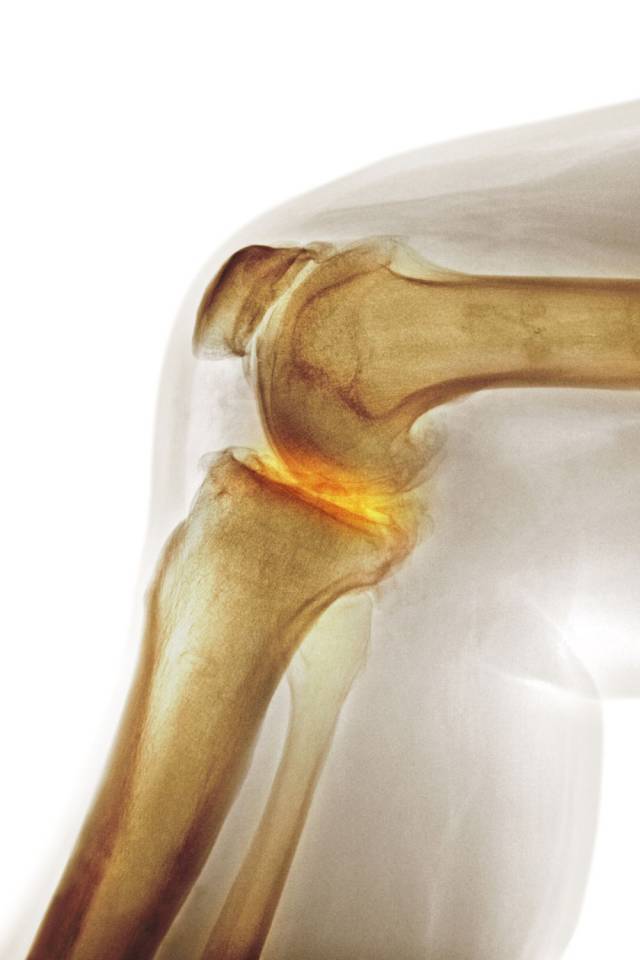

一)什么是骨髓水肿?学术上应称为骨髓水肿(bone marrow edema , BME) , 它是以骨基质水肿、纤维组织增生及炎性细胞浸润为主要病理表现的一种征象 。

二)为什么会产生骨髓水肿?骨髓水肿并不是固定一个疾病的名称 , 而是很多疾病在骨髓的共同表现 。 其主要是由病变组织血管过多、灌注过度、水的外渗作用等造成 。 目前世界公认两种形成原因:一种是继发性骨髓水肿 , 如感染、骨肿瘤、创伤、骨性关节炎、类风湿性关节炎等 , 其中以外伤性为主 。 二是生理反应性骨髓水肿 , 一些学者研究认为长期的外力作用抑或改变骨骼的正常负重 , 都会使相应骨髓产生生理反应 , 骨髓局部充血 , 毛细血管床过度灌注即骨髓水肿 。

【骨髓水肿|快船球员乔治脚部伤情:骨髓水肿】三)怎么发现骨髓水肿:首选推荐还是磁共振MRI:MRI对组织水分变化极其敏感 , 如关节软骨、关节囊、半月板、滑膜、韧带、肌肉等软组织损伤, 能为骨髓的异常改变提供重要的影像学信息 。